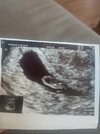

mam zdjęcie w telefoniepokażesz fotkę usg? Może masz z okresu 6-7 tc?

dzięki, Ys pecherzyk zoltkowy jest widoczny koło zarodka. Ciekawe dlaczego nie każdy lekarz dokonuje jego pomiarumam zdjęcie w telefonie